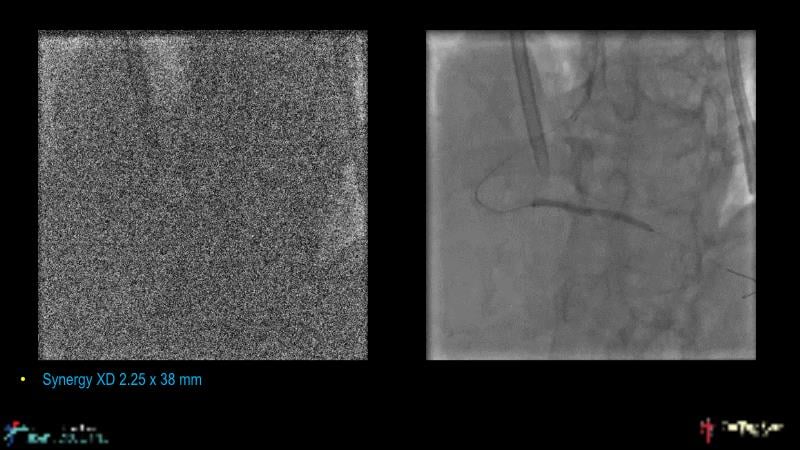

With this session, keep up to date on the evidence, trials and outcome data for intravascular lithotripsy in severely calcified lesions. Learn how to use this technique in real-world patients and understand its role in the treatment algorithm for severely calcified coronary lesions.

- To learn how to use intravascular lithotripsy in real-world patients with severely calcified coronary lesions

- To understand the appropriate role of intravascular lithotripsy in the treatment algorithm for severely calcified lesions